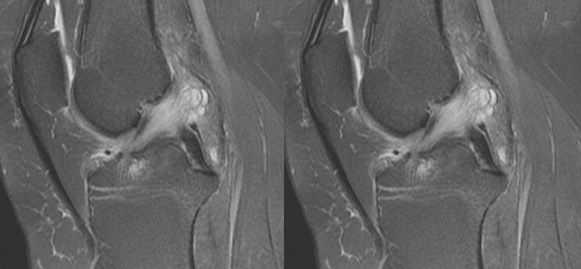

(二)ACL的正常MRI表现

各序列均为低信号。

韧带平直,边界清楚,有较好的张力。

韧带内可有脂肪及滑膜条纹影。

(四)ACL最好的观察层面

最好的观察层面是斜矢状面。

必须结合横断面和冠状面。

(五)ACL角度

矢状面ACL与髁间窝的顶部形成一个13°的夹角。